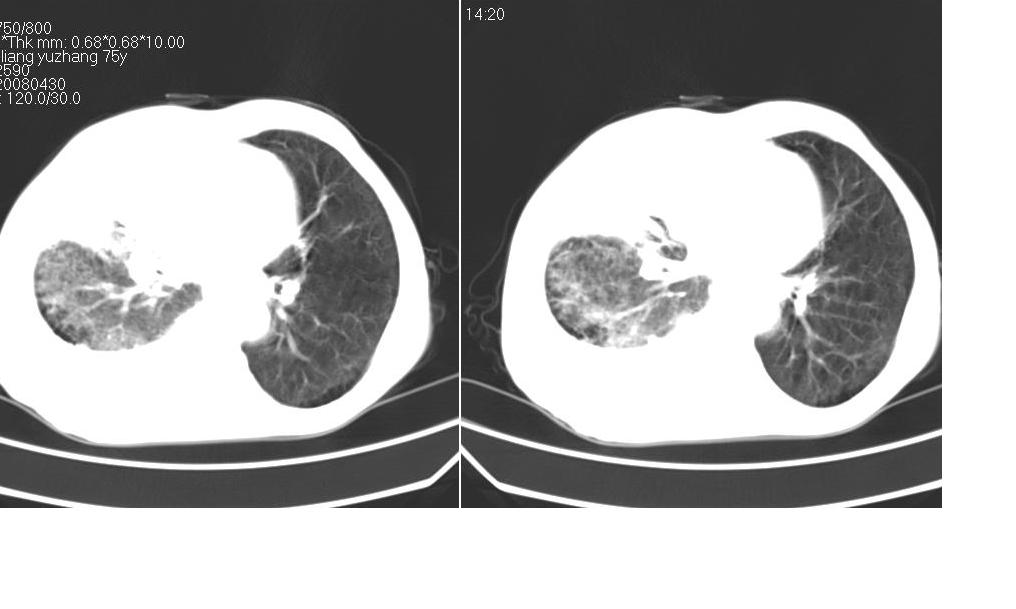

以下是引用zsl6918在2008-5-3 19:53:00的发言:[br]右肺中心型肺癌并纵隔淋巴结转移,胸膜转移,右肺癌性淋巴管炎。

以下是引用liuyue在2008-5-3 20:49:00的发言:[br]1.右侧中心型肺癌伴双肺转移瘤、纵隔淋巴结转移、右侧胸腔积液(侵及胸膜所致可能性大)。[br]2.右肺阻塞性肺炎,癌性淋巴管炎不除外。

以下是引用mzh123在2008-5-3 21:12:00的发言:[br]本人持有不同观点[br]1、右肺似有团块表现,但只有一个层面,所以本人认为还是以片为主,所以不能首先考虑肿瘤[br]2、右肺普遍成纤维化改变 并伴有片状炎症改变,和癌性淋巴管炎表现不同[br]3、所以本人认为是间质纤维化伴感染可能大 及胸腔积液